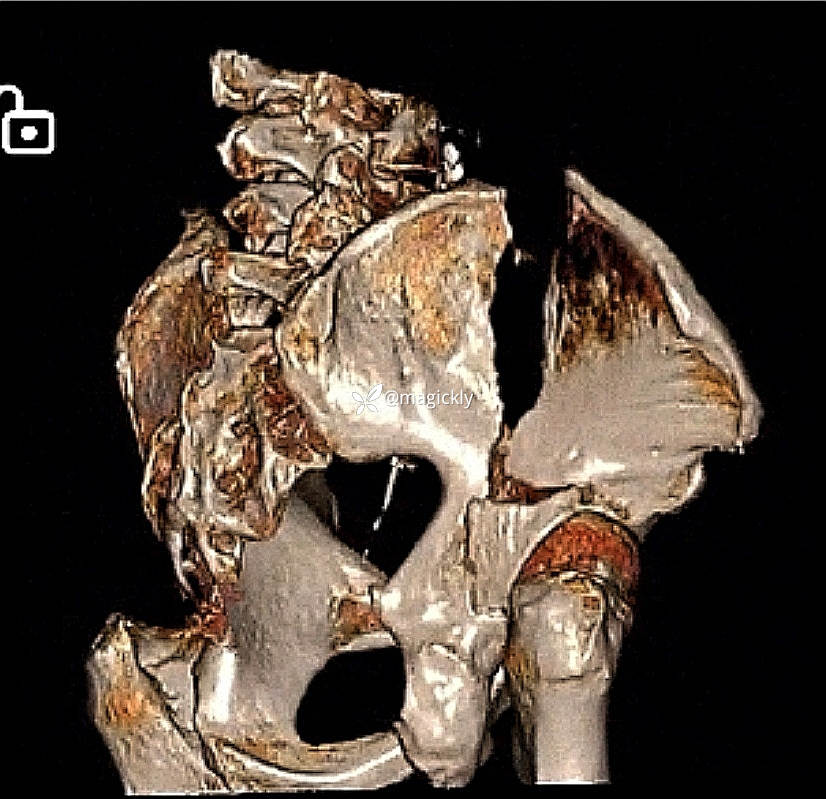

【患者信息】:男患,老年。

【主诉】:重物咋伤后右侧髋部疼痛、活动受限。

【检查】:局部体征明确,影像学结果如下

【临床诊断】:髋臼骨折(后上壁)